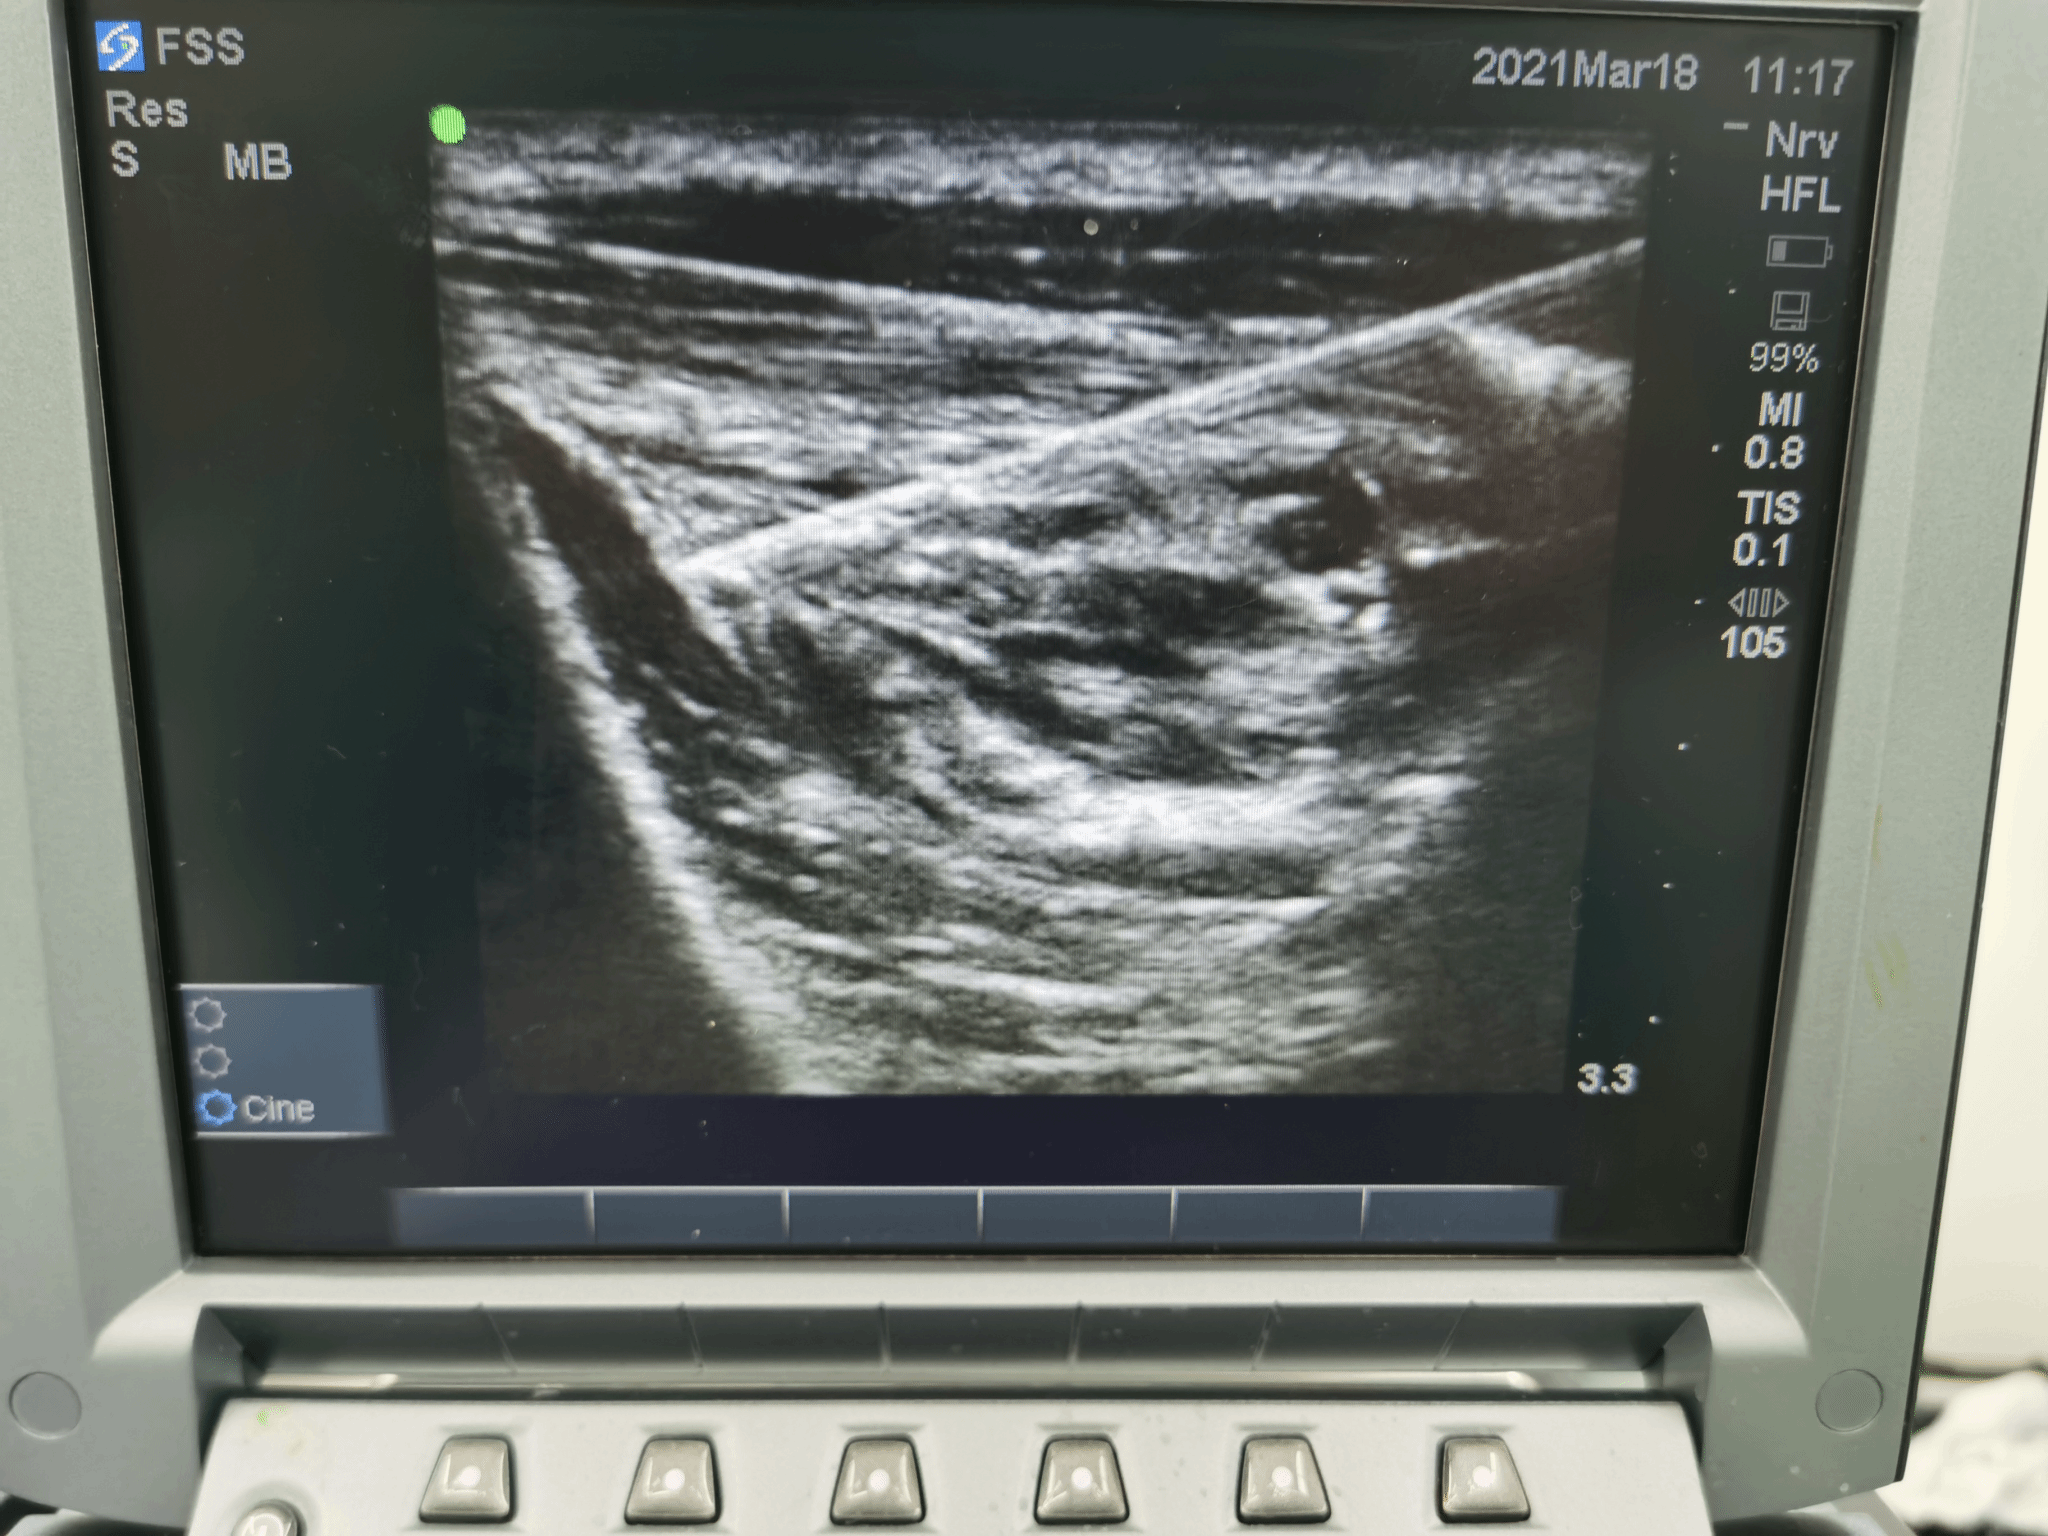

B超引导下各类神经阻滞术